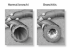

Бронхит курильщика сопровождается бронхообструкцией, которая приводит к снижению уровня оксигенации (насыщенности кислородом) крови и, как следствие, нарушению газового состава крови.